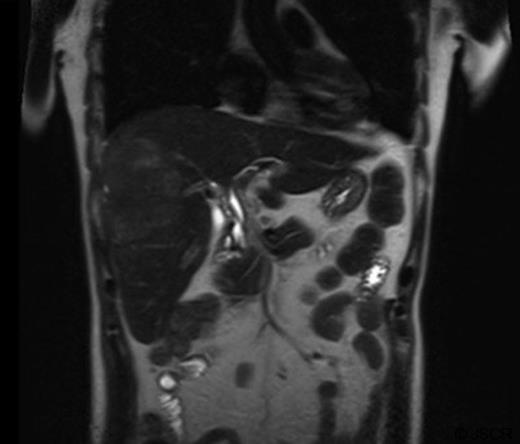

Abdominal ultrasound displayed biliary sludge although no gallstones with normal thin-walled gall-bladder. Abdominal CT-scan with contrast revealed a right liver mass involving segments V to VIII measuring 10.6cm×6cm axially and 10cm craniocaudally with mild caudate lobe hypertrophy suggesting underlying cirrhosis; intra-hepatic bile duct dilation, subcapsular fluid and lymphadenopathy (figure 1).

The mass had mild hyperintense signal on T2-weighted images and capsule retraction, suggesting a scirrhous lesion (figure 3); possibly cholangiocarcinoma.

T2 weighted abdominal MRI, coronal view displaying right lobe liver mass.